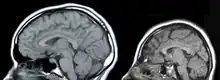

The nervous system is divided into two sections: the CNS and the PNS. The CNS consists of the brain and the spinal cord, while the PNS consists of nerves that originate from the brain and spinal cord and innervate the rest of the body.[1]

There are three main causes of CNS injury: stroke, traumatic brain injury (TBI), or developmental complications. Strokes are classified as either hemorrhagic (when a vessel is damaged to the point of bleeding into the brain) or ischemic (when a clot blocks the blood flow through the vessel in the brain). When a hemorrhage occurs, blood seeps into the surrounding tissue, resulting in tissue death, while ischemic hemorrhages result in a lack of blood flow to certain tissues. Traumatic brain injury is caused by external forces impacting the cranium or the spinal cord. Problems with CNS development results in abnormal tissue growth during development, thus decreasing the function of the CNS.[3]